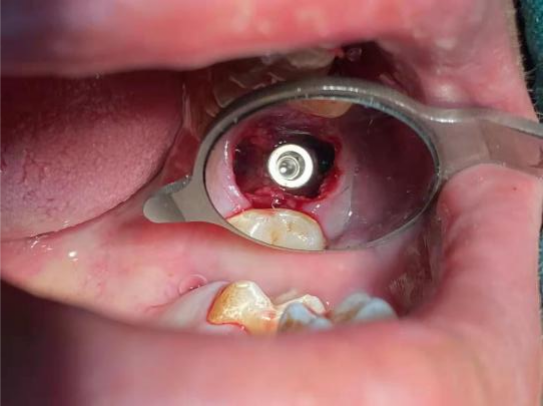

基台安装完成后